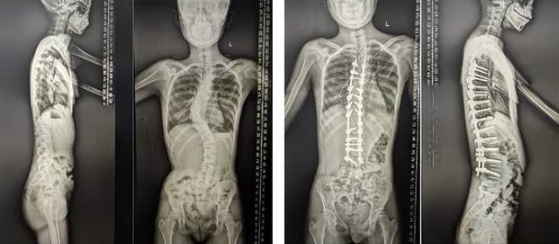

7月26日,邱勇院士、史本龙教授与脊柱外科团队为一名预约的青少年特发性脊柱侧弯的患者成功实施了脊柱矫形手术,术后患者很快恢复了正常体态,已出院进行功能锻炼,并为新学年的学习生活积极准备。

“以青少年特发性脊柱侧凸手术为例,手术的目标不仅是矫正脊柱的侧弯畸形,还要考虑肩平衡、矢状位平衡等问题,同时尽可能减少对患者脊柱生长发育的影响,让患者在术后能够恢复正常的体态和生活质量。”史本龙教授介绍,“往往通过手术治疗,患者的脊柱畸形将得到显著改善,身体外观将更加挺拔,心肺功能也可能得到一定程度的提升,有利于患者更早的重新融入正常社会生活。”

除了提供门诊看诊服务,史本龙教授还将为预约的患者完成脊柱矫形手术治疗。脊柱矫形手术是脊柱外科领域中技术难度极高的手术之一,它对于医生的技术水平、手术经验以及医院的设备条件都有着严苛的要求。几年来,每次手术前,集团脊柱外科杨希重主任团队联合鼓楼专家团队,对患者的病情进行深入分析,结合患者的年龄、身体状况、脊柱畸形的类型和程度等诸多方面因素,制定个性化的手术方案。同时,在手术过程中,整个团队会借助先进的医疗设备,如三维导航系统及术中神经电生理监测设备等,实时精确术中操作及监测,确保手术操作的精准性和安全性,最大程度降低手术风险,减少对患者脊髓和神经的损伤。